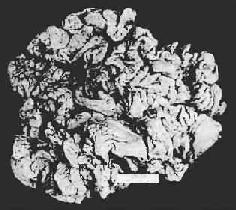

慢性萎缩性胃炎

图10-3 慢性萎缩性胃炎

幽门腺大部分萎缩消失,胃小凹延长,有潴留性小囊形成,腺上皮中杂有不少杯状细胞(肠上皮化生),固有膜内有不少慢性炎性细胞浸润(Ⅱ74-4950)